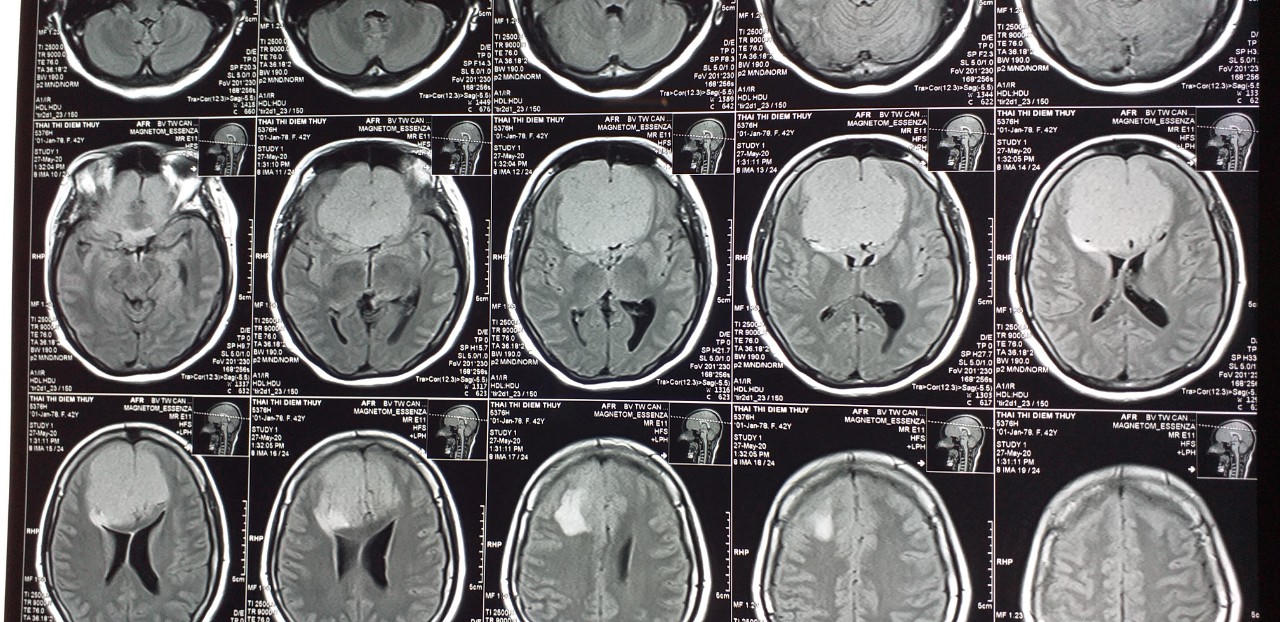

Các bác sĩ tiến hành khám lâm sàng kết hợp cận lâm sàng kiểm tra. Kết quả kết luận u màng não khổng lồ. Các bác sĩ tiến hành hội chẩn quyết định chụp và nút mạch tiền phẫu số xóa nền nhằm mục tiêu tắc mạch máu nuôi khối u.

Các bác sĩ đã bóc tách, lấy sạch khối u ra khỏi sàn sọ, gửi mẫu bệnh phẩm sinh thiết tế bào. Đến ngày 12/6, bệnh nhân tỉnh, tiếp xúc được, không yếu liệt chi, mắt nhìn rõ, vết mổ khô, giảm đau đầu nhiều.